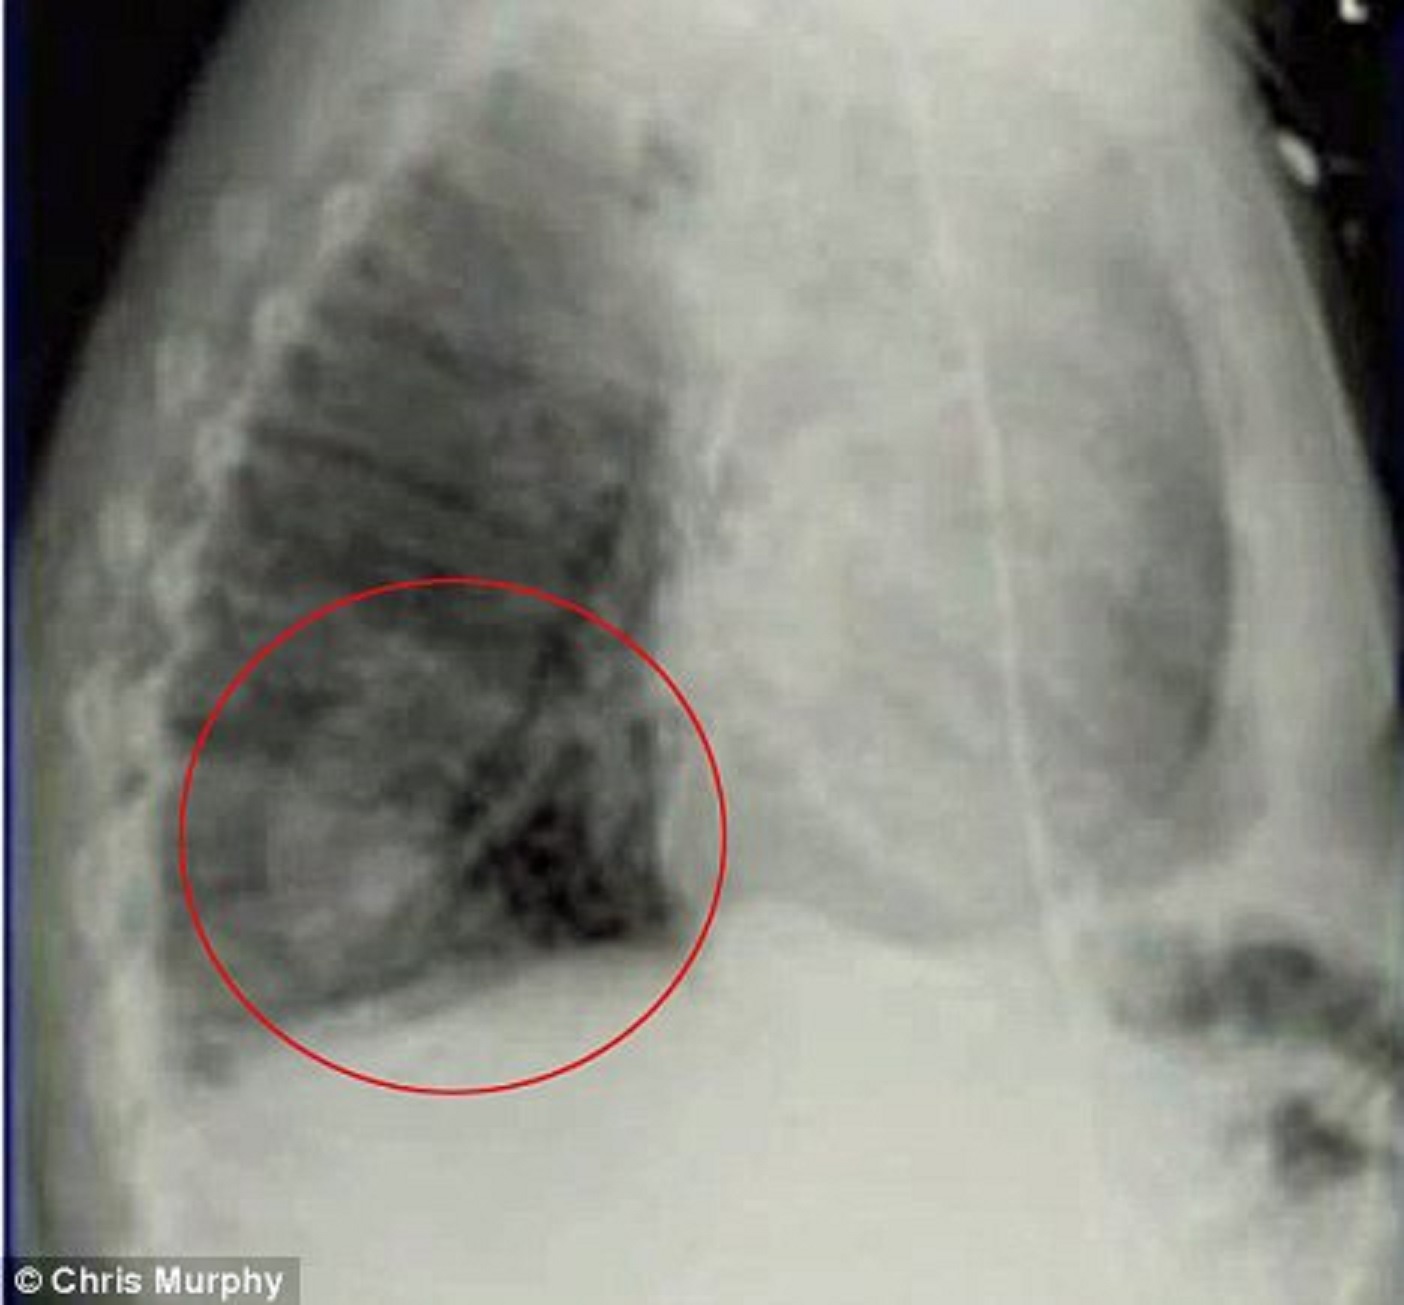

| Một quả lựu đạn nổ chậm mắc kẹt trong hông binh sĩ Pakistan. Ảnh: Daily Mail |

Channing Moss là một binh nhất trong quân đội Afghanistan. Năm 2011, một nhóm người đã dùng lựu đạn tấn công bất ngờ khi anh cùng đồng đội đang tuần tra ở khu vực giao tranh. Một quả lựu đạn sức công phá mạnh có khả năng giết chết tất cả những ai trong phạm vi 9 mét bay về phía họ. Tuy nhiên, nó không phát nổ mà mắc kẹt bên hông Moss. Nhân viên y tế trong đội nhanh chóng chăm sóc anh và gọi cấp cứu. Tuy nhiên, nạn nhân phải chờ đợi nhiều giờ trong đau đớn vì trực thăng không thể nhanh chóng tiếp cận khu vực giao tranh. May thay, bất chấp nguy cơ quả lựu đạn có thể phát nổ bất cứ lúc nào, phi hành đoàn quyết định làm trái quy định và đưa anh đến bệnh viện gần nhất.

Khi đến bệnh viện, tim nạn nhân đã ngừng đập do mất máu quá nhiều. May mắn hơn, một trong số ít các chuyên gia phá bom cũng có mặt tại bệnh viện vào lúc đó và đã kích nổ quả lựu đạn tại một địa điểm an toàn. Nhờ sự cố gắng không mệt mỏi của các bác sĩ, Moss dần hồi phục và có thể đi lại, theo Daily Mail.

Channing Moss trở thành anh hùng sau vụ sống sót kỳ diệu. Quân đội Afghanistan trao tặng anh Huy chương Purple Heart, huy chương dành cho binh sĩ bị thương trong chiến đấu, và Huy chương Dũng cảm.